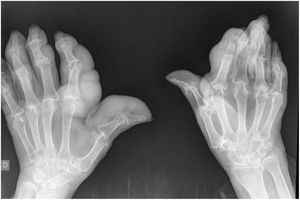

She visited our surgery due to arthralgia in the hands and feet with a crisis of pain and functional impotency in multiple joints that has evolved over more than 15 years. Physical examination found major tophaceous deposits in the hands and feet, most strikingly in the right hand (Fig. 1), with incapacity of grasping, above all in the right hand.

Bone X-ray imaging showed an important increase in the soft parts, with trapping and erosion in the metacarpophalangeal, proximal and distal interphalangeal joints of both hands (Fig. 2), as well as erosion on the first metatarsal joints and luxation of the 5th left metatarsal joint (Fig. 3).